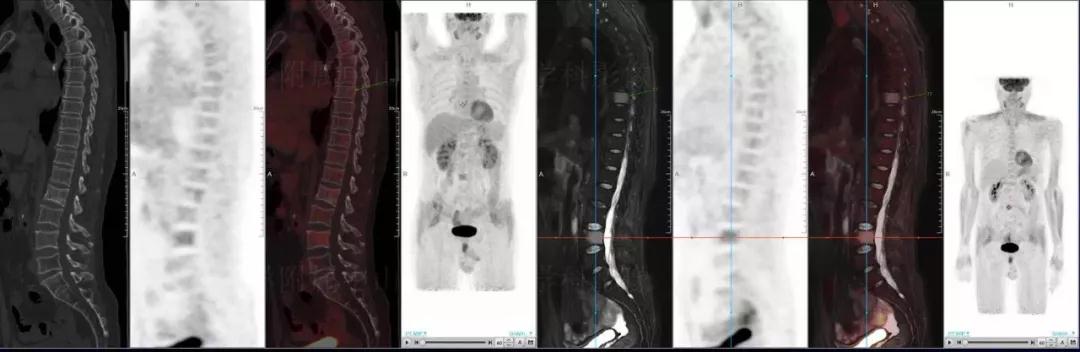

多發(fā)性骨髓瘤

中山醫(yī)院核醫(yī)學(xué)科基于聯(lián)影“時(shí)空一體”超清TOF PET/MR的融合顯像優(yōu)勢(shì),進(jìn)行了大量的臨床掃描,發(fā)現(xiàn)多例由MGUS向多發(fā)性骨髓瘤轉(zhuǎn)變,并從中總結(jié)出了一定的共同征象,未來(lái)可能實(shí)現(xiàn)多發(fā)性骨髓瘤的早期篩查。此外,PET/MR在多發(fā)性骨髓瘤的療效評(píng)估方面,也存在顯著優(yōu)勢(shì)。

(男性,53歲。確診多發(fā)性骨髓瘤10月。經(jīng)過(guò)7周期VCD方案化療后,現(xiàn)行療效評(píng)價(jià)。)